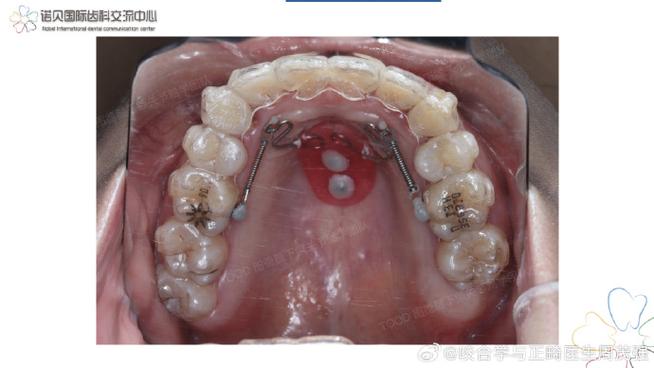

RW技术通过在腭部放置可调节扩弓装置(如Hyrax扩弓器或Haas扩弓器),利用持续轻力(通常每次加力0.5-1.0mm,每日1次)作用于上颌骨,促使腭中缝(青春期前为软骨,青春期后逐渐骨化)分离,并诱导新骨沉积,从而增加上颌骨横向宽度,这一过程不仅扩大牙弓、纠正后牙反颌,还能调整咬合接触点,改善下颌运动轨迹,进而影响颞下颌关节的生物力学环境,TMD常与咬合干扰、牙弓宽度不协调相关:例如上颌狭窄导致后牙反颌,下颌咀嚼时偏向一侧,造成双侧咀嚼肌力失衡,髁突在关节窝内受力不均,长期负荷过载可引发关节炎症、疼痛甚至关节盘移位,RW通过建立稳定的咬合接触、消除下颌偏斜,恢复咀嚼肌群对称性协调,减轻关节机械应力,从而缓解TMD症状。

临床实施RW治疗TMD需遵循标准化流程:首先是诊断评估,通过临床检查(关节触诊、开口度测量、咬合分析)、影像学检查(CBCT观察髁突位置、关节间隙、腭中缝状态)及肌电图评估肌肉功能,明确TMD类型及咬合问题,其次是装置选择,根据患者年龄、牙弓形态选择Hyrax(带环固位)或Haas(基托覆盖腭部)扩弓器,扩弓阶段需控制加力频率(每日1次)及力量(0.5-1.0mm/次),维持2-3周至后牙建立稳定咬合接触,期间每周复诊监测装置稳定性及牙齿移动情况,扩弓完成后需保持3-6个月,使用可摘式保持器或固定保持器维持牙弓宽度,随后进入固定矫治阶段排齐牙列、调整咬合关系,总疗程通常1.5-2年。